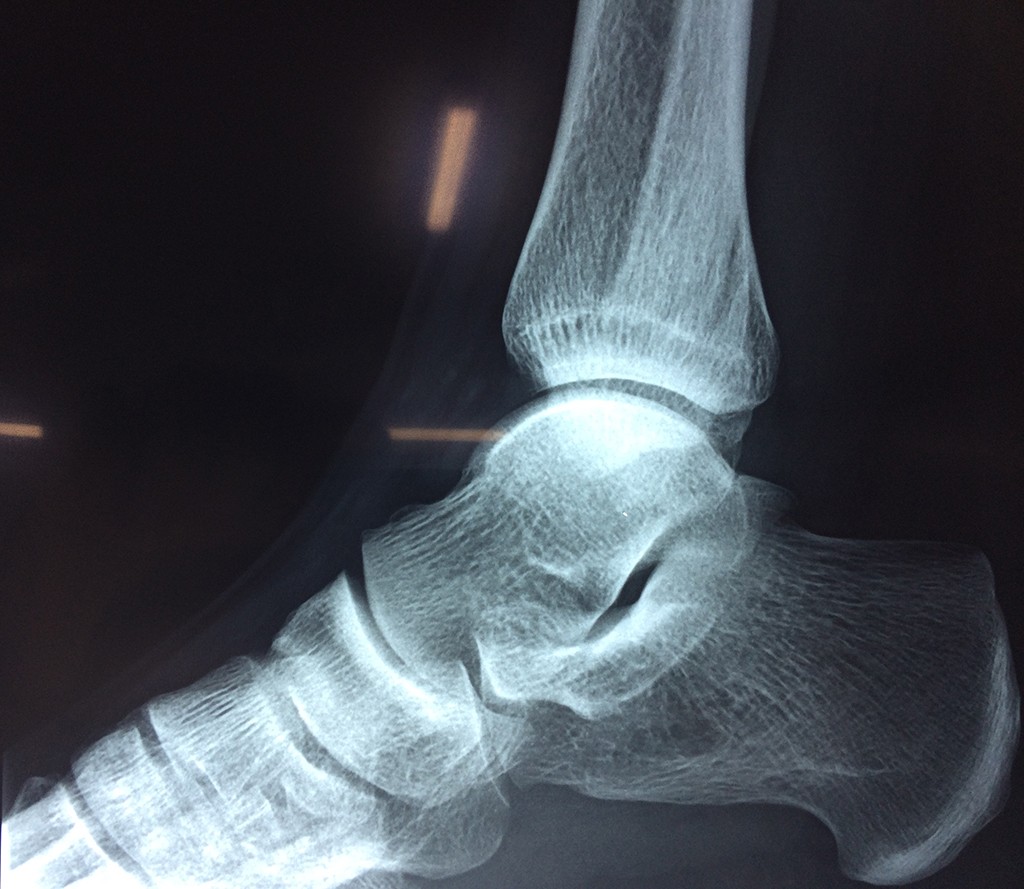

Una fractura de tobillo es la rotura de uno o más de los huesos del tobillo. Estas fracturas pueden ser:

- La fractura se extiende hasta la articulación del tobillo (fractura intra-articular).